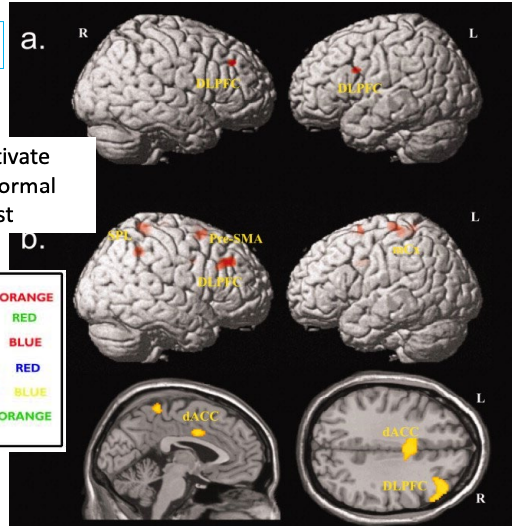

OCD patients activate DLPFC more than normal during Stroop test

Overthinking.

OCD patients have increased activity in orbital frontal cortex and caudate nuclei (basal ganglia)

Surgery to disconnect Orbitofrontal cortex from anterior cingulate cortex produces long lasting improvement.